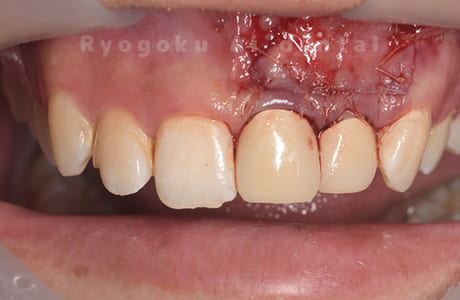

前歯の腫れが治らない、とのことでご来院された患者様です。前歯には他院で自費で入れた被せ物が入っており、被せ物のやり変えと共に根管治療の提案を致しましたが、このままの状態での治療を希望されたため、歯根端切除術を行いました。手術後の痕も気にならずに、腫れもなくなり、非常に満足して頂きました。半年経過を追っておりますが、現在も再発等ございません。

<リスク・副作用>

外科手術のため、術後に出血、痛みや腫れ、違和感を伴います。口腔内の状態によっては適応できないことがあります。歯根端切除で治らなければ抜歯を検討しなくていけない場合もあります。